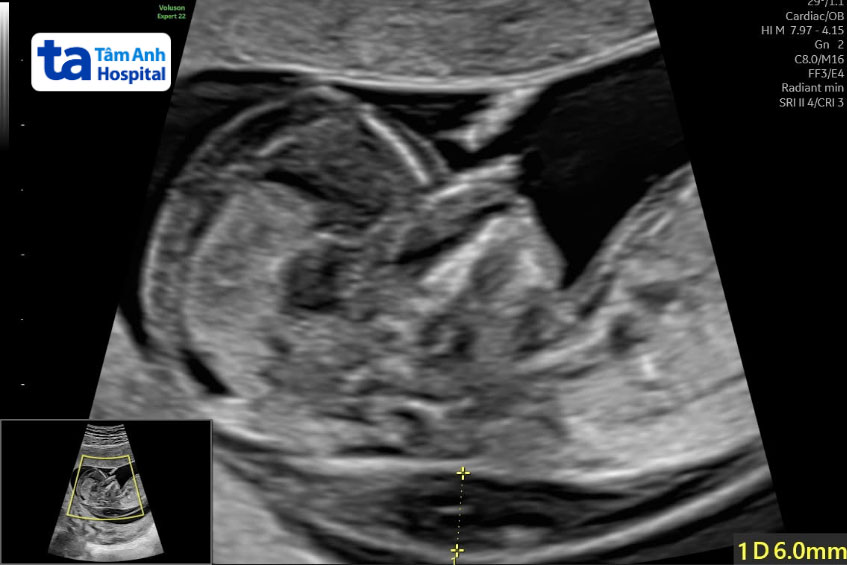

BS.CKI Nguyễn Thị Mộng Nghi, Trung tâm Y học bào thai, Bệnh viện Đa khoa Tâm Anh TP.HCM, cho biết thai phụ 30 tuổi, mang thai lần đầu, siêu âm lúc 13 tuần ghi nhận độ mờ da gáy dày 6 mm (dưới 3 mm là bình thường), thai nhi có nang bạch huyết vùng cổ sau kích thước 10x3x13 mm, phù da vùng đầu và thân.

Hai đột biến gene FOXC2 và RAF1 xảy ra cùng lúc rất hiếm gặp, có khả năng là đột biến mới hoặc di truyền từ bố mẹ, bác sĩ tư vấn xét nghiệm di truyền cho bố mẹ nhưng thai phụ không đồng ý vì lý do cá nhân. Một tuần sau bác sĩ Nghi siêu âm kiểm tra lại, kết quả thai phù toàn thân nhiều hơn, nếp gấp da gáy 12,3 mm, nang bạch huyết vùng cổ sau tăng lên 16x6x20mm. Bác sĩ Nghi đánh giá tình trạng thai nhi tiến triển nặng hơn, các dấu hiệu bất thường của các cơ quan khác có thể xuất hiện theo thời gian. Các bất thường này làm tăng tỷ lệ thai lưu, trẻ tử vong trong hoặc sau sinh. Do đó, gia đình xin đình chỉ thai kỳ ở tuần thai 15.